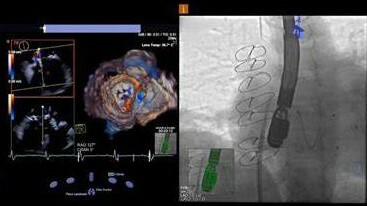

• Modern Transesophageal Echocardiogram

Modern Transesophageal Echocardiogram

TEEs require placing the probe into the mouth to access the esophagus. The esophagus is located directly behind the heart's left atrium, where the ultrasound probe can closely evaluate important structures within the heart. TEE's are used in many implantable cardiac device procedures.